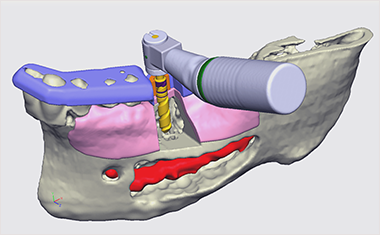

BioNaシミュレーション画像

BioNaシミュレーション画像 歯牙支持型フラップレス

歯牙支持型フラップレス